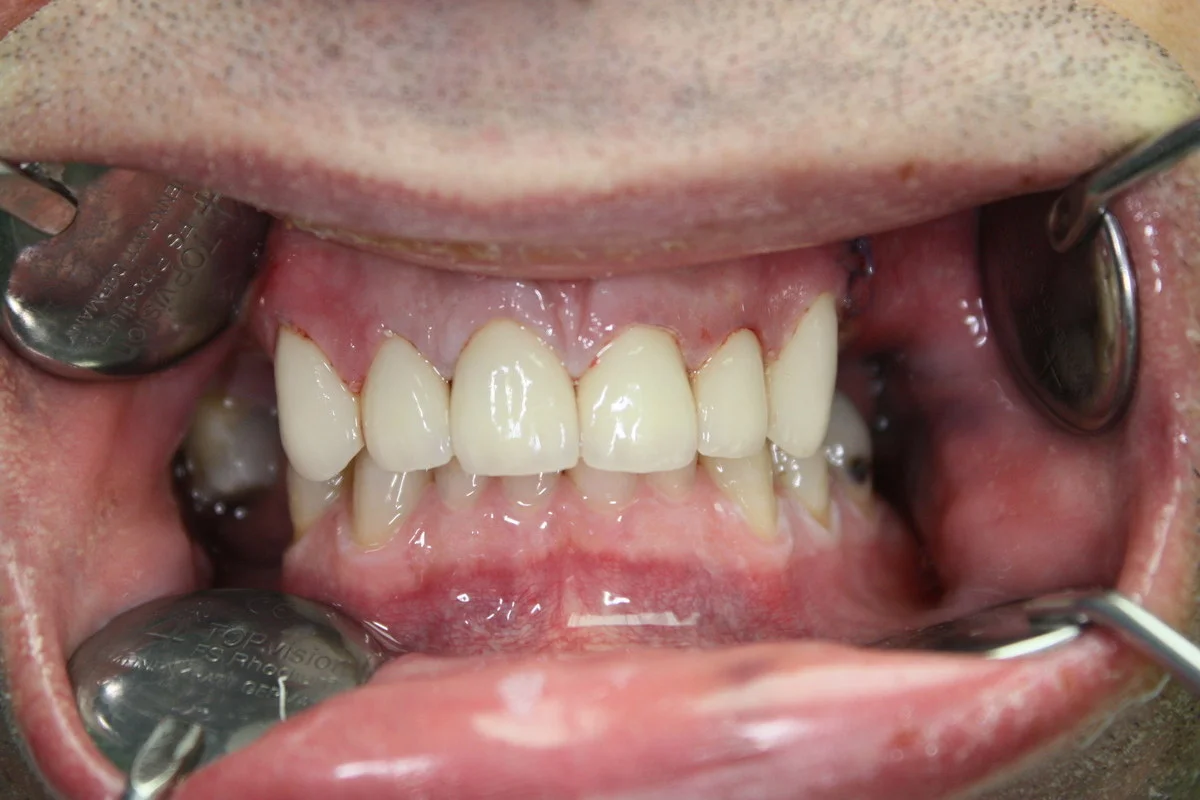

In the case of extensive tooth loss involving several teeth next to each other, our dentists recommend the use of monolithic zirconium or porcelain zirconium bridges to the frontal area. These metal-free bridges are individually made, their colors match the color and shape of your natural teeth. The difference between natural teeth and the bridge units is practically zero, unnoticeable.